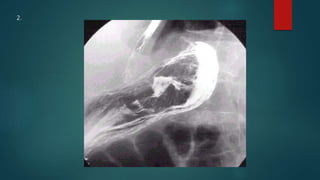

This document appears to be a medical report discussing several patients. It mentions a 35-year-old who was in a severe motor vehicle accident and an 81-year-old with a history of a non-vegetarian diet who had a perforated bowel from a chicken bone. The document provides few other details across its 25 numbered entries and was authored by Dr. Anish Choudhary for junior year 3 on May 30, 2016.